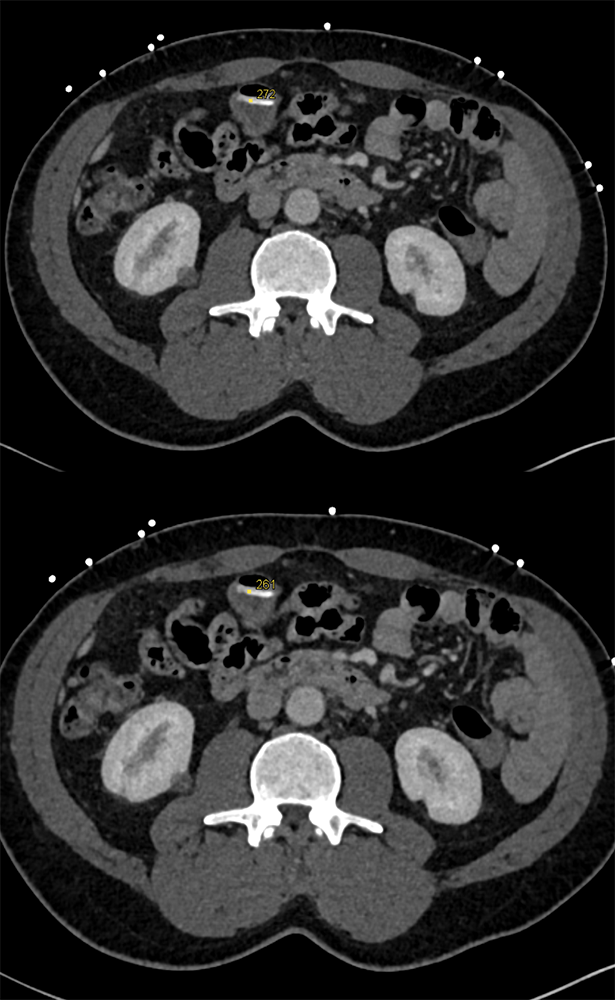

GI Bleed in Patient with Crohn’s and had Atrial Fib on Anticoagulants ![]() |

![]() |